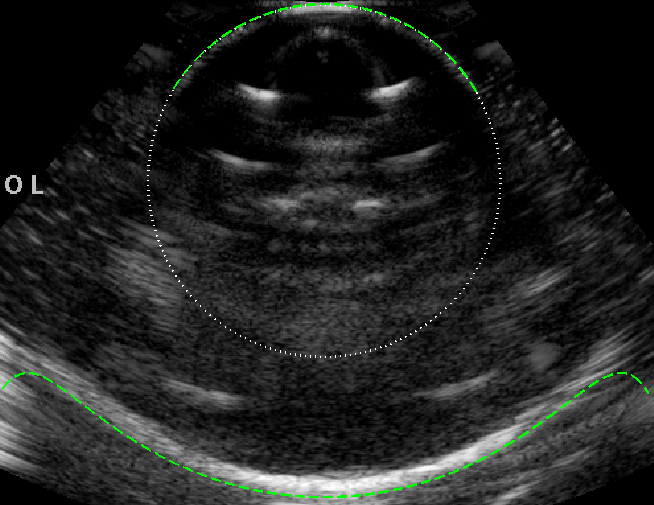

Experimental B-mode images (with curved array) of the circular test object are shown in figure 5, alongside the ray model predictions, for following 3 speed of sound scenarios.

(b) v2v1much-less-thansubscript𝑣2subscript𝑣1v_{2}\ll v_{1}: Now taking v2=1100subscript𝑣21100v_{2}=1100 m s-1 (methanol) gives the more extreme case of v2/v1=0.71subscript𝑣2subscript𝑣10.71v_{2}/v_{1}=0.71. The far-face of the image is highly distorted, in good agreement with the ray model.

(a)                                  (b)                                  (c)

Refer to caption Refer to caption Refer to caption

Figure 5: B-mode images of the circular object of speed v2subscript𝑣2v_{2} (imaged from above in a liquid with speed v1subscript𝑣1v_{1}), with the ray model superimposed (green dashed line). (a) v2=1490subscript𝑣21490v_{2}=1490 m s-1 and v1=1540subscript𝑣11540v_{1}=1540 m s-1, giving v2/v1=0.968subscript𝑣2subscript𝑣10.968v_{2}/v_{1}=0.968. (b) v2=1100subscript𝑣21100v_{2}=1100 m s-1 and v1=1540subscript𝑣11540v_{1}=1540 m s-1, giving v2/v1=0.71subscript𝑣2subscript𝑣10.71v_{2}/v_{1}=0.71. (c) v1=1490subscript𝑣11490v_{1}=1490 m s-1 and v2=1540subscript𝑣21540v_{2}=1540 m s-1, giving v2/v1=1.034subscript𝑣2subscript𝑣11.034v_{2}/v_{1}=1.034.